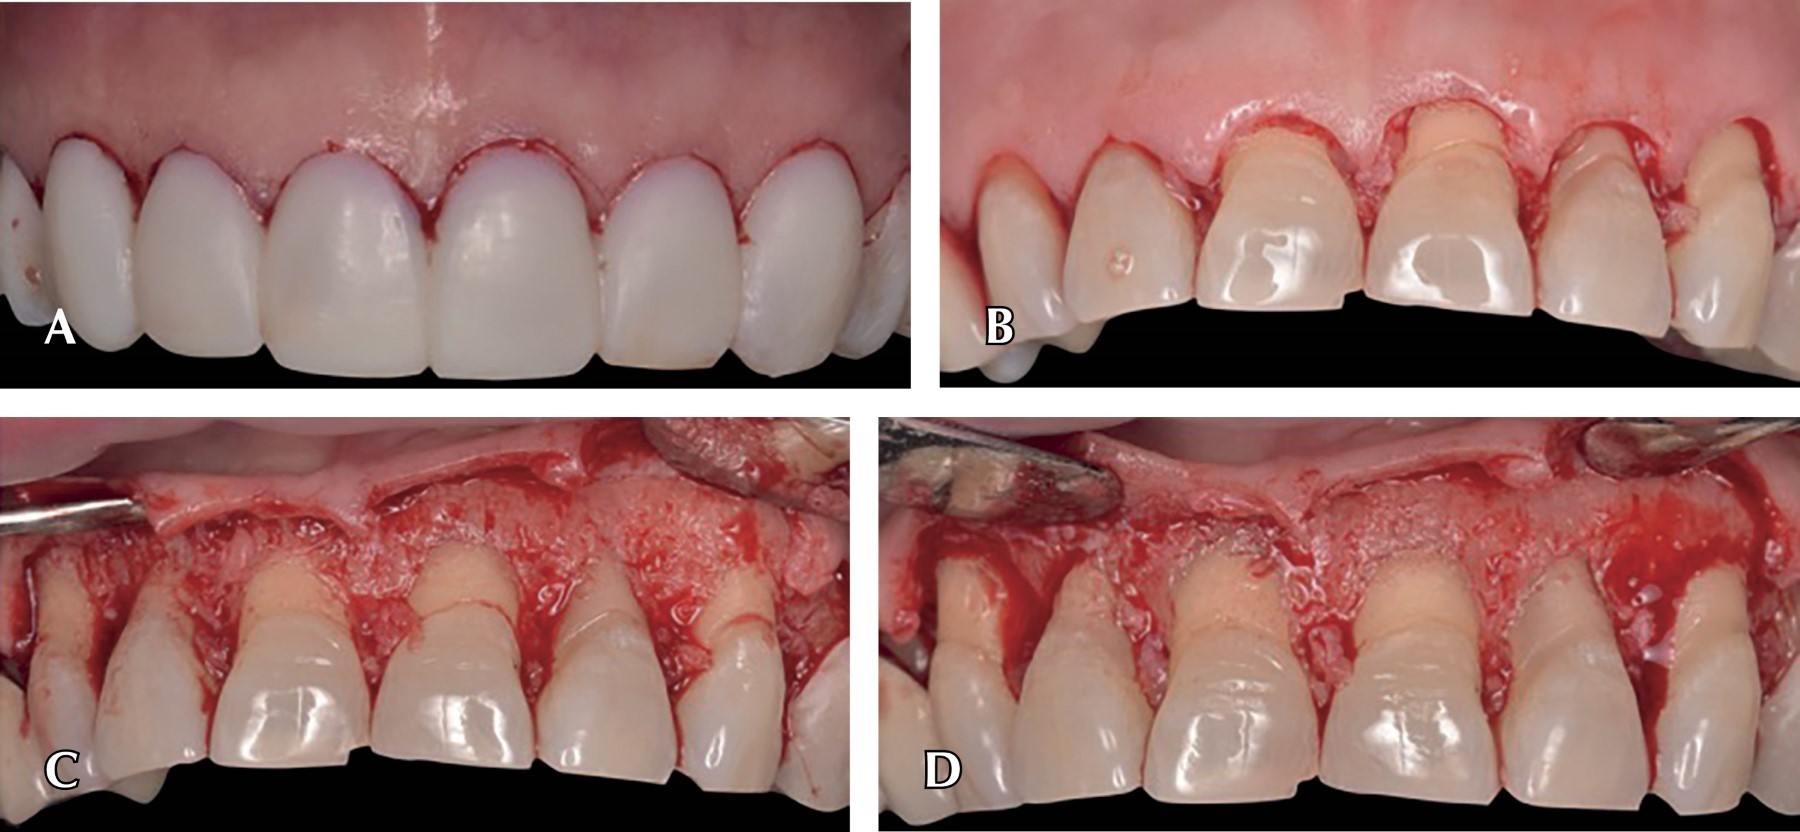

Introduction: the digital flow has reinvented processes in dentistry, from diagnostic methods to surgical protocols. The precision and brevity offered by digitalization has encouraged research and incorporation by the clinic to speed up time and reduce errors in dental treatments. The goal is to introduce even more digital flow in surgical procedures to reduce the operating time for the patient and the operator. Clinical case: a 70-year-old female patient, ASA I, referred by the Prosthodontics Department for crown lengthening in order to achieve compensation of the dentogingival tissues with the occlusal plane correction through the use of crown lengthening previously planned in EXOCAD. Pre and transoperative time was reduced, obtaining a more accurate symmetrical smile and gingival margin without compromising occlusion and periodontal tissues. Computer-aided design and manufacturing broadens the perspectives in a treatment plan, three diagnostic methods such as tomography, intraoral scanning and facial photographs are used together to perform a digital wax-up and articulator.

Figure 2